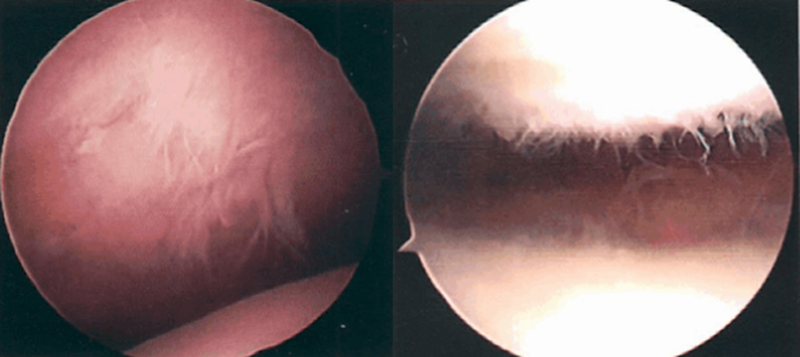

关节镜下可将髌骨软化分为5级

0级:正常关节软骨

Ⅰ级:关节软骨失去珍珠样外观而变得较暗淡,局部软化,肿胀区或纤毛化区的直径<0.5cm。

Ⅱ级:关节软骨软化区内出现毛刷状或纤毛化改变,深达1-2mm,直径≤1.3cm。

Ⅲ级:软骨的毛刷状或纤毛化改变达关节软骨厚度一半以上,直径>1.3cm,关节软骨表面类似蟹肉样改变,表面有多发软骨碎片附着其下的软骨。

Ⅳ级:关节软骨全层受侵,软骨下骨暴露,表现为进展期髌股关节炎。

Ⅰ~Ⅱ级为早期,主要保守治疗,Ⅲ~Ⅳ级为进展期,需要手术及关节镜治疗。

髌骨软化症Ⅲ级

髌骨软化症Ⅳ级